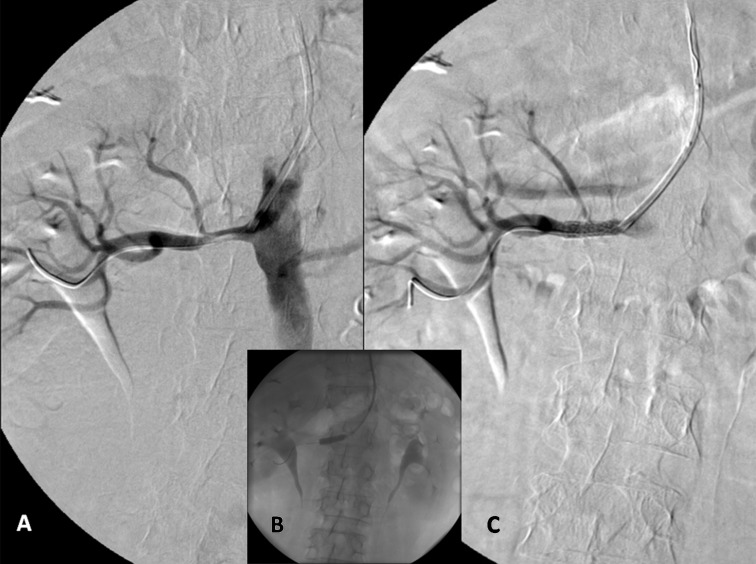

Fig. 1.

A: High grade stenosis of the left renal artery and selective cannulation with a Multipurpose 6F guiding catheter. B: Direct stenting with a 6 × 18 mm Herculink stent. C: Final result